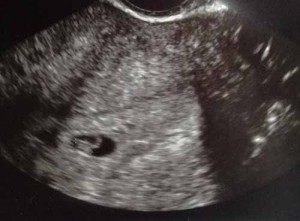

I just saw my doctor yesterday for the sonogram and everything looked great. I am 6 weeks and 2 days . My HCG levels were 165 at 3 weeks and 3000 at 4 weeks.